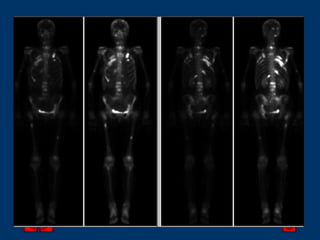

< 5% das cintilografias são normais em pacientes com lesões vistas no RX 10-40% dos pacientes com metástases ósseas têm RX normal e cintilografia alterada Em 30% dos pacientes com tumor conhecido se apresentando com dor e RX normal a cintilografia óssea mostra lesões metastáticas O RX é pouco sensível, e pode demorar 6 meses para evidenciar resposta, além de ser difícil avaliar a resposta em lesões inicialmente escleróticas. Cintilografia Óssea Cintilografia x RX

Exames bem feitos e com boa qualidade tem alta sensibilidade e especificidade 260 Pacientes 1191 Rastreamentos 10 anos de follow up Sensibilidade: 98,2% Especificidade: 95,2% Acurácia: 95,5% VPP: 72,8% VPN: 99,8% Cintilografia Óssea Interpretação J Nucl Biol Med 1993; 37:57–61

Cintilografia óssea Metástases são mais comuns em pacientes com níveis altos de PSA e tumores pouco diferenciados na biópsia, independente da idade A cintilografia deve ser realizada se o PSA for > 20 ng/ml em pacientes com histologia G1 ou G2, e em pacientes com histologia G3 e doença localmente avançada, independente do PSA A cintilografia óssea não é necessária em pacientes com tumores iniciais, PSA < 20 ng/ml e Gleason <=7, a não ser que haja sintomas sugestivos de metástases Não é necessário realizar cintilografia de rotina no follow-up se não houver mudança nos marcadores séricos ou sintomas sugestivos de metástases A cintilografia óssea deve ser realizada quando há alterações rápidas nos marcadores ou quando há surgimento de quaisquer sintomas